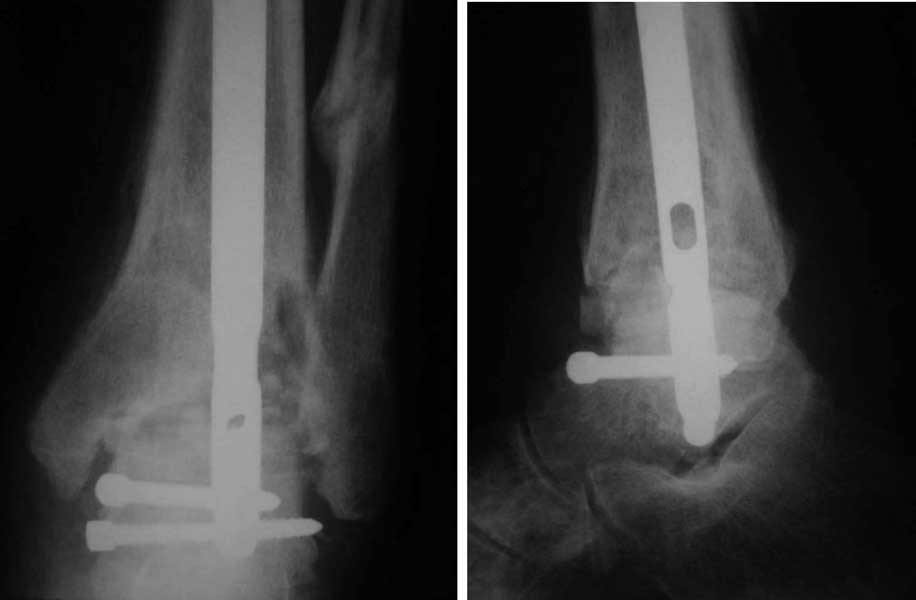

Интересный случай. Допускаю, что состояние мягких тканей приемлемое. Цель лечения должна заключаться, как мне кажется, в ликвидации ложного сустава и достижении артродеза голеностопного сустава. Впрочем, это две взаимосвязанные задачи. Мы бы оперировали следующим образом. Остеотомия малоберцовой кости на вершине деформации. Передне-медиальным доступом артротомия голеностопного сустава, резекция суставных поверхностей с отломков большеберцовой и таранной костей, удаление рубцов между отломками дистального эпиметафиза большеберцовой кости, антеградный стержень с дистальным блокированием в таранной кости, костная пластика дефекта спонгиозным костным трансплантатом из крыла (возможно сразу из двух) подвздошной кости. Банальные артродезы голеностопного сустава мы обычно выполняем антеградным блокированным стержнем (см. вложенный файл),

что позволяет сохранить подтаранный сустав, и нагружать ногу сразу после операции.